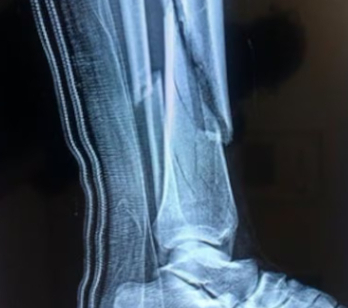

Xolani slipped, fell, and almost drowned in the pool. He is said to have been rescued by a neighbour who heard the screams. He was rushed to a nearby hospital. He underwent surgery on his leg and is set to have another surgery performed on the same leg.